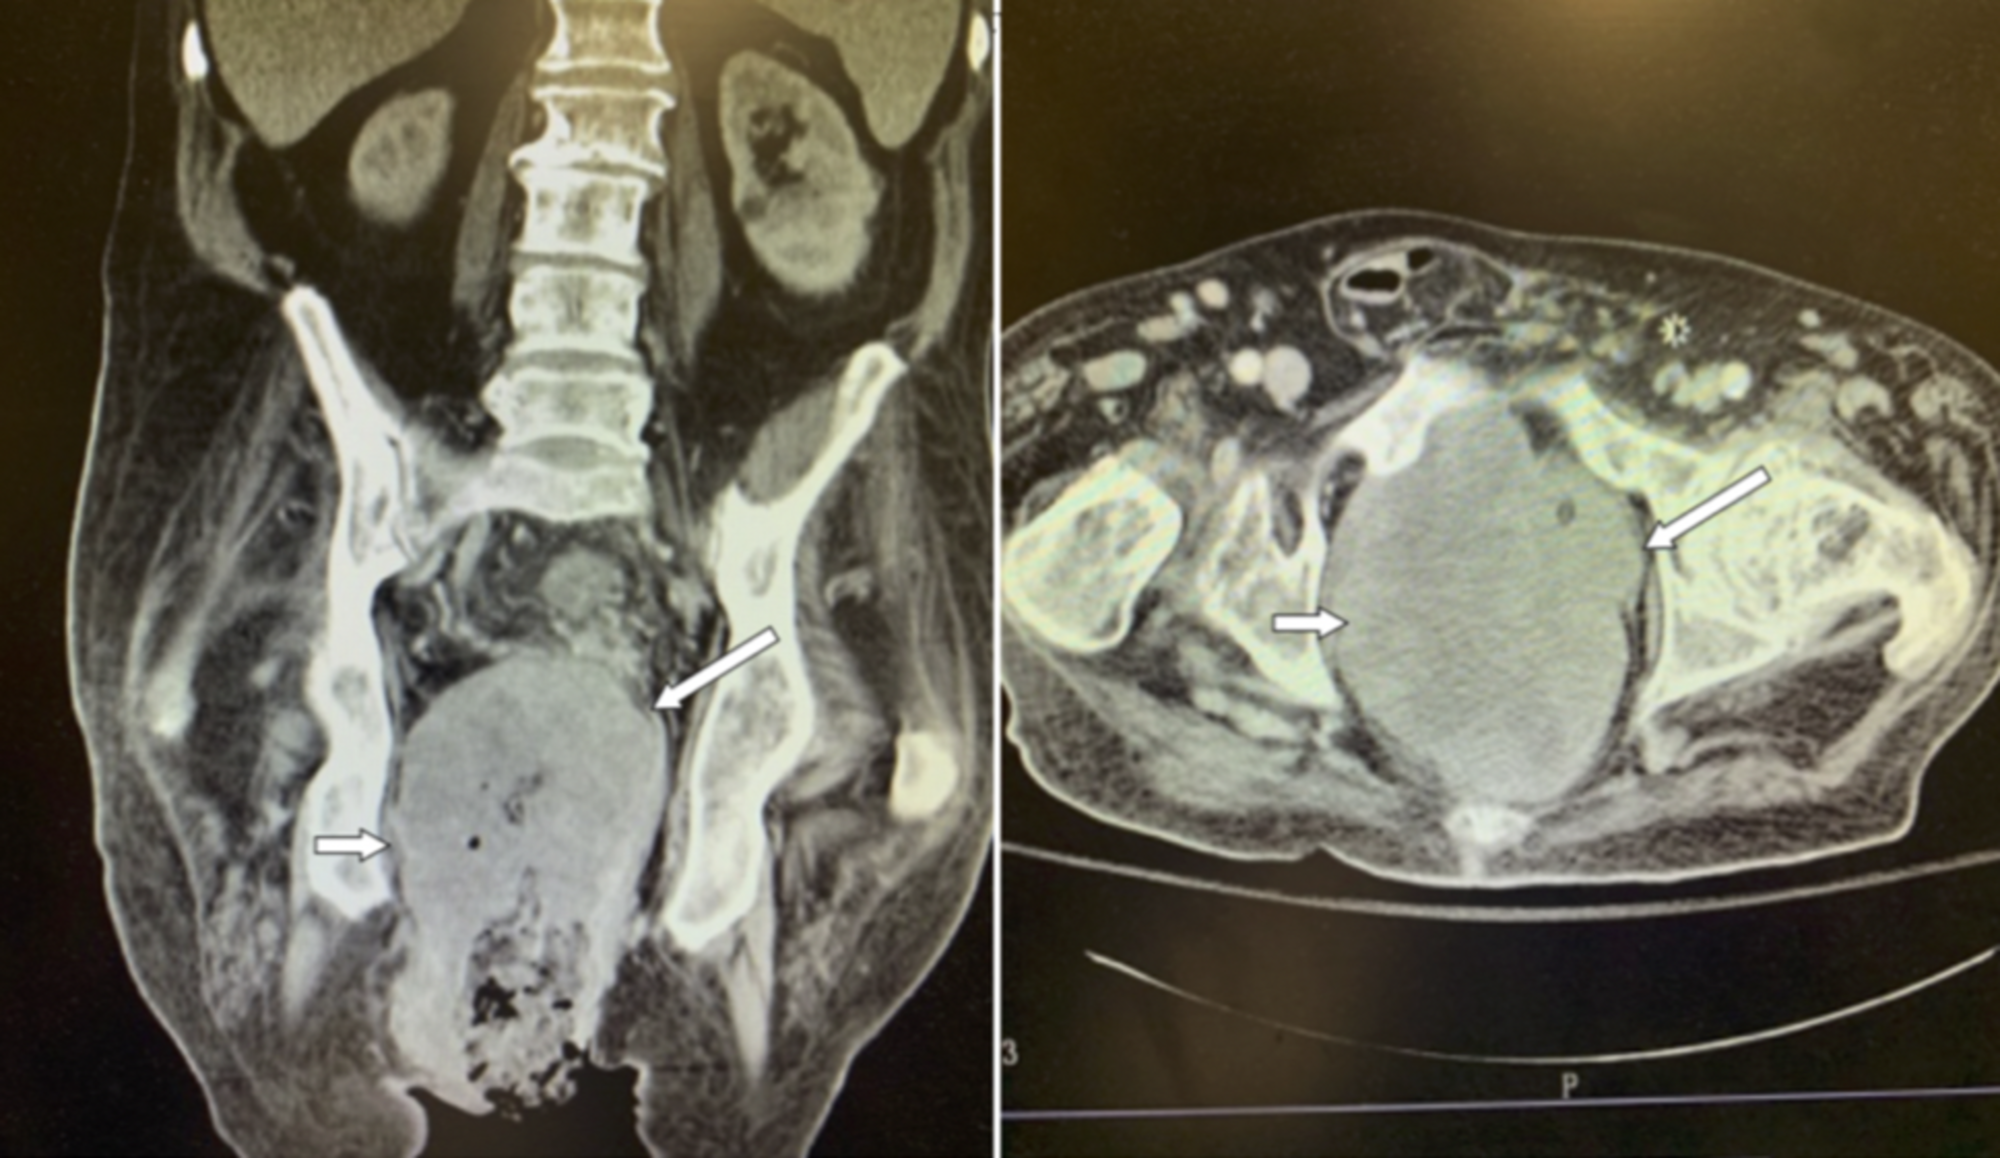

Fournier’s Gangrene in a Female Diabetic Patient A Case Report Cureus Fournier S Gangrene On Ct Fournier gangrene, a relatively rare form of necrotizing fasciitis, is a rapidly progressive disease that affects the deep and superficial. Fournier gangrene (fg) is a genitourinary necrotizing fasciitis that is fatal if not promptly diagnosed and surgically débrided. Fournier’s gangrene is a rapidly progressive necrotizing fasciitis of the genital and perineal tissues with a high mortality rate. The fournier's gangrene. Fournier S Gangrene On Ct.

Fournier’s Gangrene CT Annotated. JETem 2022 JETem Fournier S Gangrene On Ct Fournier gangrene, a relatively rare form of necrotizing fasciitis, is a rapidly progressive disease that affects the deep and superficial. Fournier's gangrene is a rare but potentially fatal disease. Fournier’s gangrene is a rapidly progressive necrotizing fasciitis of the genital and perineal tissues with a high mortality rate. In this pictorial review, we discuss the pathogenesis of fournier gangrene and. Fournier S Gangrene On Ct.